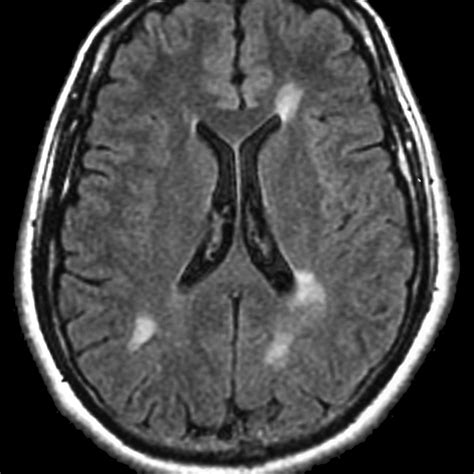

• Autoimmune and Inflammatory Conditions: Diseases like Multiple Sclerosis (MS) frequently cause demyelinating lesions.

⚠️ Note: It is very common to have "unidentified bright objects" (UBOs) or nonspecific lesions on an MRI, especially as we age. Many of these are considered incidental findings that do not cause any clinical symptoms.

Typically, the first step is an MRI with and without contrast. The contrast dye helps radiologists distinguish between different types of tissue and can highlight active inflammation or tumor blood supply. Blood tests may also be ordered to rule out systemic autoimmune diseases, infections, or metabolic issues.